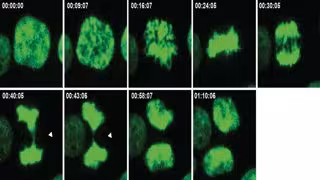

Proceso de división celular con errores.

Proceso de división celular con errores. - SHELTZER LAB/CSHL, 2020